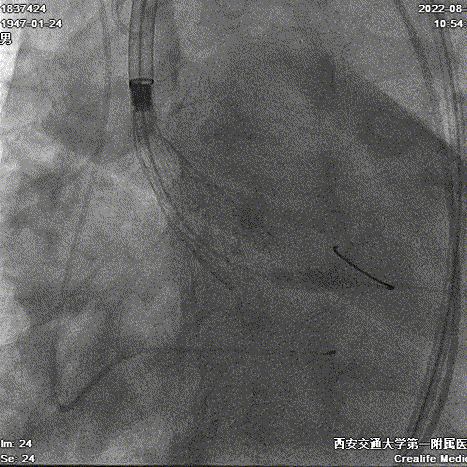

球囊预扩张

球扩后发现20mm球囊并未将瓣环开口填满,球囊没有显现收腰,且有明显瓣周漏,因此团队决定采用Evolut PRO 29mm瓣膜。